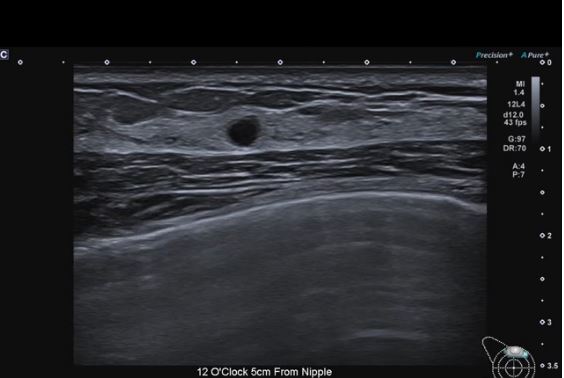

Precision+ Режим точної обробки

Precision+ відомий своєю видатною продуктивністю у створенні однорідних зображень із чіткими контурами, покращеною рівномірністю зображення та зменшенням артефактів. Новий режим Fine Processing Aplio beyond забезпечує ще чистіші зображення з більш чіткими контурами.

Клінічні зображення